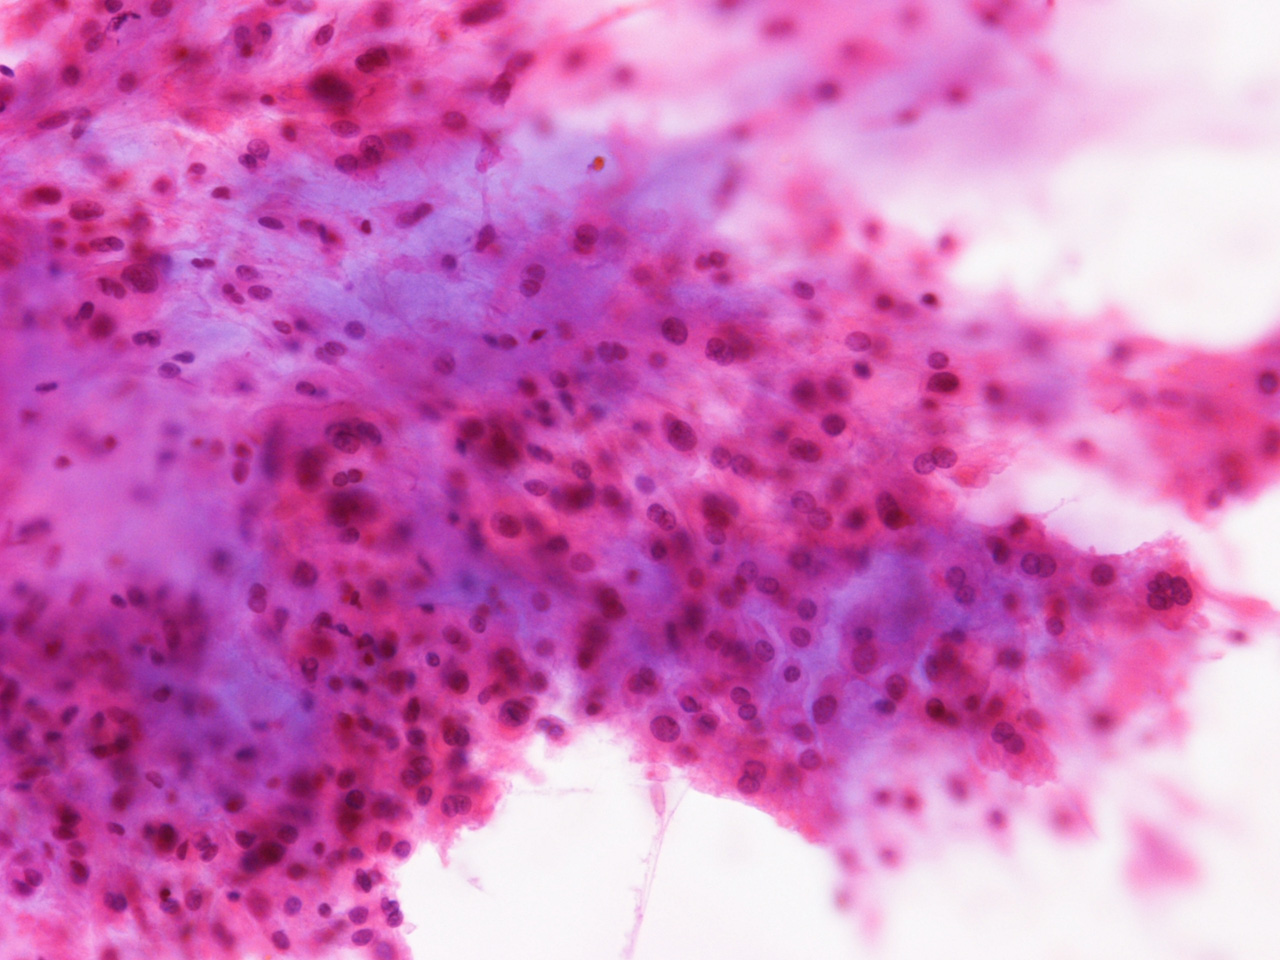

At the time of operation, a cytologic squash preparation (H&E) was prepared (Panels BC, and D). On low magnification, the lesion is composed of large clusters of eosinophilic cells with centrally located nuclei. There is some bluish acellular substance admixed with the tumor cells (Panel B). If you pay attention, some of the cells are arranged in short chains (arrows in Panel C). This is a frequently seen phenomenon in chordoma. On high magnification, the cells have centrally located medium sized to large, hyperchromatic nuclei. The cytoplasm is finely eosinophilic but not particularly bubbly  (Panel D). The frozen sections (Panels E and Freflect the cytologic features. The tumor is composed of solid sheets of large tumor cells admixed with small amount of fibrous areas, mild chronic inflammatory cell infiltration and hemosiderin depositions (Panel E). On high magnification, the tumor cells are admixed with bluish extracellular material.  The cytoplasm is coarsely granular with fine bubbles. The permanent sections (Panel G and Hshow similar features. And the bubbly cytoplasm is more prominent in the permanent sections (Panel H). Focal bone invasion is present (Panel I). The cytoplasmic vacuoles are best appreciated in the semithin section (Panel M). Results of special studies are as follows:

The characteristic histologic findings in chordomas are large polygonal cells with distinct cell membrane and the vacuolated physaliphorous cytoplasm, the term deriving from the Greek physalis, or "bubble. The vacuolated or physaliphorous cells are best appreciated in cytologic smears or squash preparations. Tumor cells grow in small nests and cords within a myxoid/chondroid matrix and demonstrate round, sometimes rather uniform nuclei with low nuclear-to-cytoplasmic ratios. The tumor cells tend to adhere into clusters and cords. The classic large physaliphorous cell has a centrally located nucleus surrounded by a narrow rim of cytoplasm that in turn, is encircled by a ring of more peripherally located cytoplasmic vacuoles. Nuclear grade is not particularly high in some cases but many of them have clearly recognizable nuclear pleomorphism. Occasional large, atypical cells are present. These nuclear changes should not be present in benign notochordal cell tumor and ecchordosis physaliphora/fetal vestige [Amer & Hameed, 2010]

On cytologic smears [Crapanzano JP et al., 2001], chordoma cells tend to be cohesive but not as cohesive to each other as carcinomas. Strings of chordomas are common features.